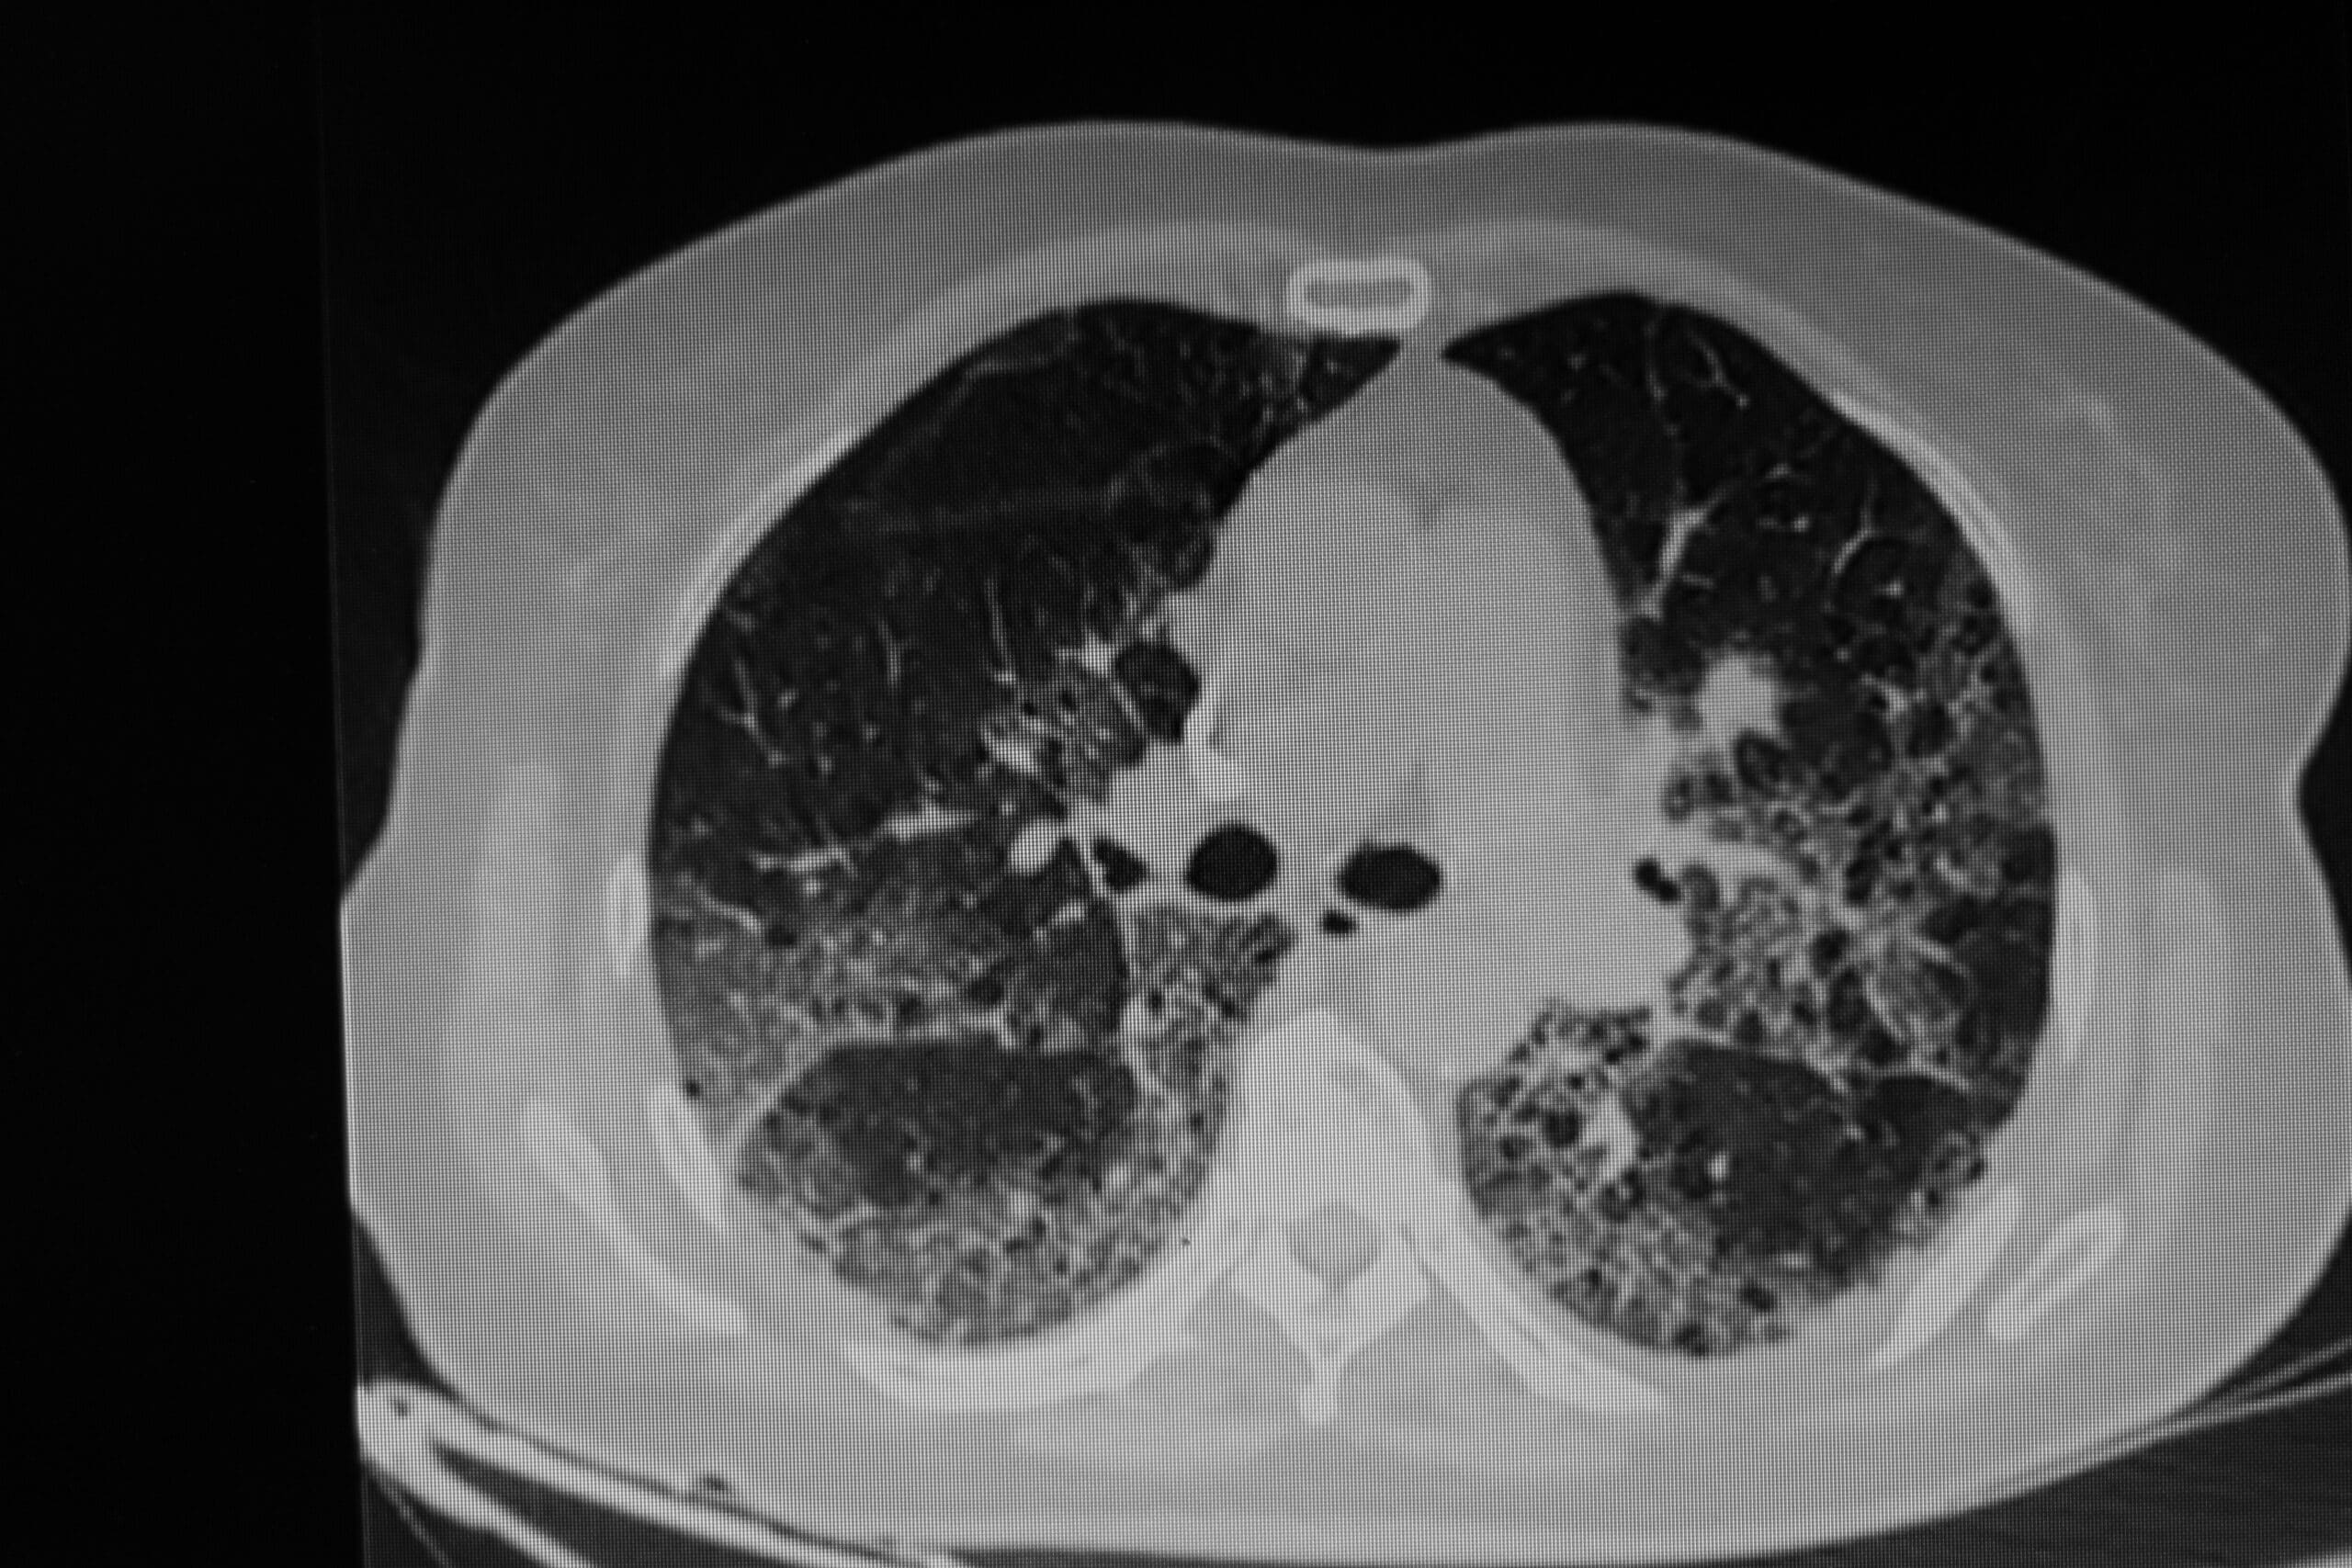

Interstitial pneumonia expresses as a ground glass appearance on a chest X-ray, typically appearing hazy and diffuse. It sometimes presents as a honeycomb because the pneumonia isn’t consolidated to one lobe or lung.

A chest X-ray highlighting ground-glass opacities.